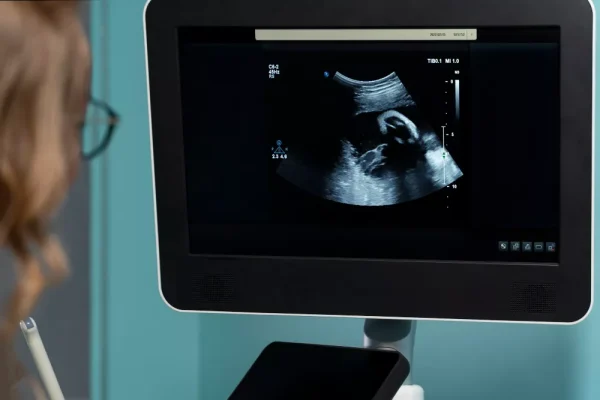

- Tetkikler

- Hizmetler